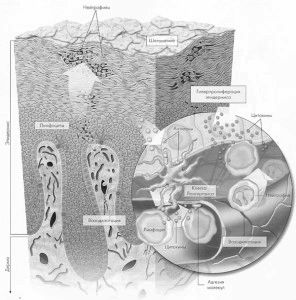

Найчастіше вражаються шкірні покриви, але в рідкісних випадках можуть дивуватися нігті або суглоби (псоріатичний артрит). Найчастіше псоріаз у дітей виглядає як безліч папул, що мають тенденцію до злиття, після яких утворюються бляшки. Папули представляють собою маленькі осередки хронічного запалення з надлишковою проліферацією кератиноцитів, макрофіт і лімфоцитів. Також в уражених ділянках відбувається посилений ангіогенез (утворення безлічі дрібних судин).

Псоріаз у дітей є другим за значимістю захворюванням після атопічного дерматиту. Як показують статистичні дослідження, пусковим фактором активації псоріазу є гострі інфекційні хвороби, важкі емоційні і фізичні стреси. Також причиною виникнення можуть бути харчові фактори (алергічні реакції на продукти), особливо схильні до цього діти, схильні до розвитку діатезу. Доведено, що захворювання передається від батьків дітям.